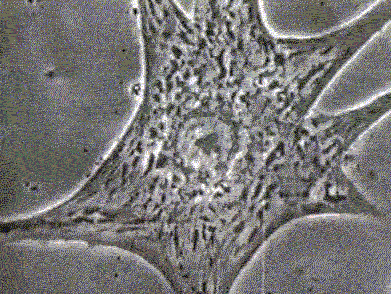

6.乳腺癌细胞。